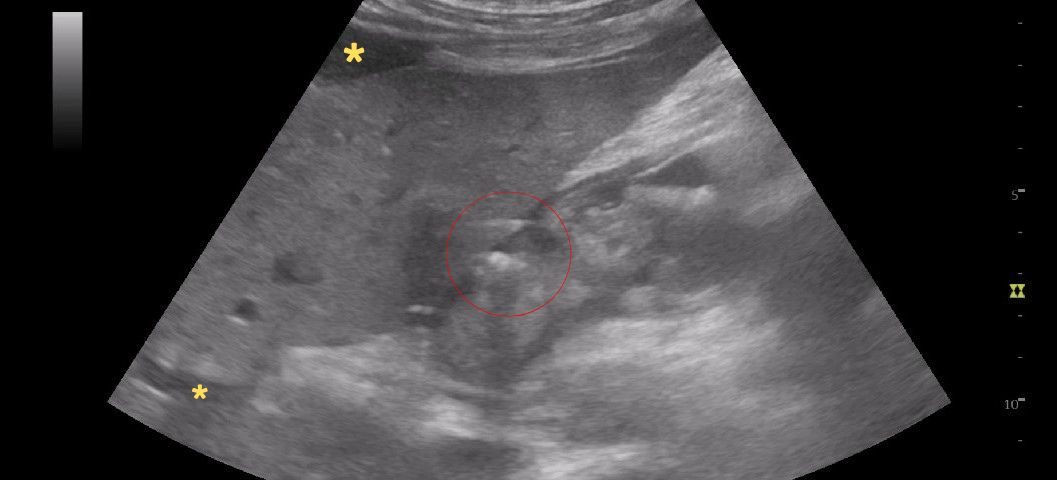

FIGURE 1 and VIDEO 2: Ultrasonography demonstrates the presence of free fluid within the peritoneal recesses, predominantly in the perihepatic and subhepatic regions (yellow asterisks). The fluid appears mildly echogenic, suggestive of inflammatory exudate rather than simple transudate. The duodenal bulb (D1 segment) is thickened and edematous. The area outlined in red demonstrates multiple hyperechoic foci with reverberation artifacts consistent with extraluminal free gas, adjacent to a focal mucosal wall defect. These findings are highly suggestive of a perforated duodenal ulcer.

FIGURE 1 and VIDEO 2: Ultrasonography demonstrates the presence of free fluid within the peritoneal recesses, predominantly in the perihepatic and subhepatic regions (yellow asterisks). The fluid appears mildly echogenic, suggestive of inflammatory exudate rather than simple transudate.

The duodenal bulb (D1 segment) is thickened and edematous. The area outlined in red demonstrates multiple hyperechoic foci with reverberation artifacts consistent with extraluminal free gas, adjacent to a focal mucosal wall defect. These findings are highly suggestive of a perforated duodenal ulcer.